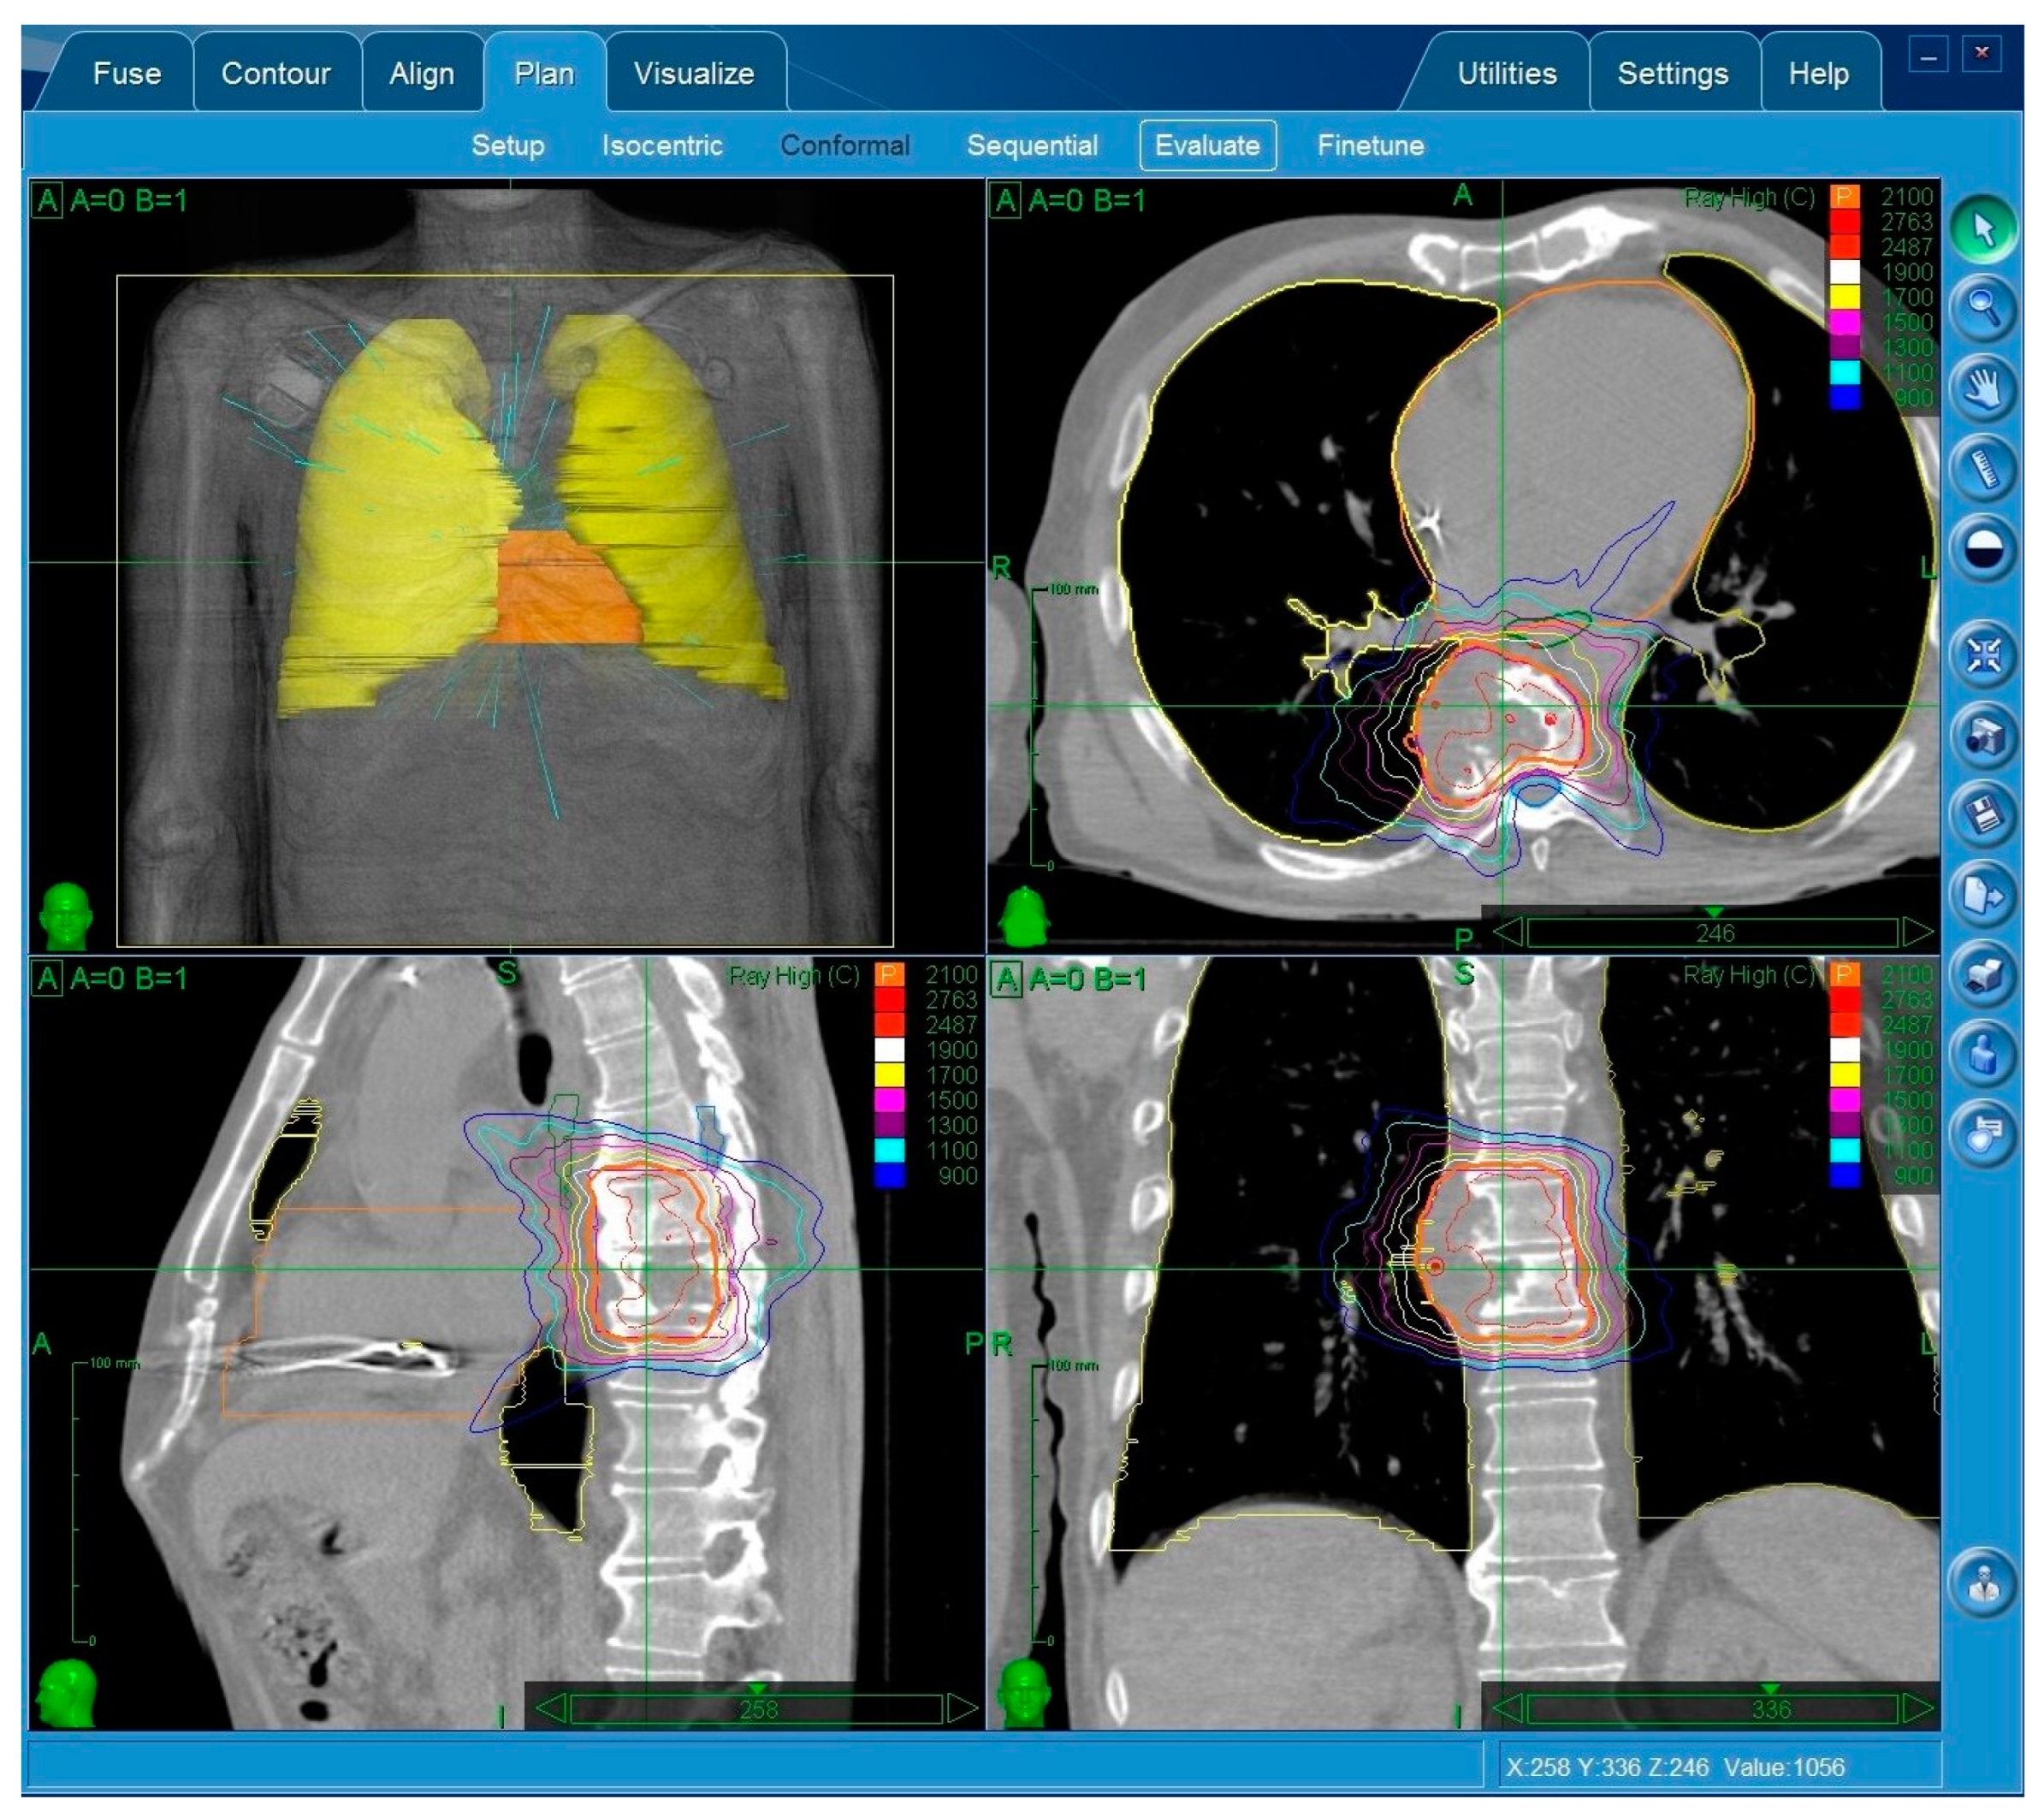

2.1. Treatment Planning